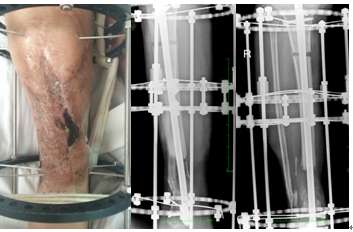

手术案例 —左胫骨创伤后骨髓炎